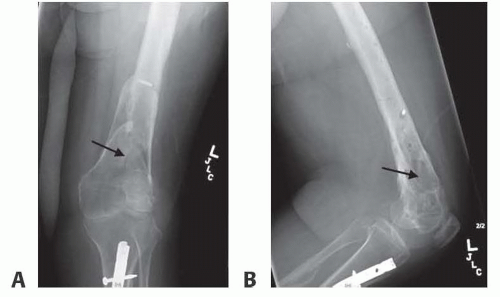

Plain radiographs can demonstrate nonhealing bone, erosive cortical changes seen in acute infection, and sclerotic thickening seen in chronic infection (FIG 1).

CT scan is best for bony detail. It is the modality of choice to identify a nidus of dead bone (sequestrum) and surrounding sclerotic bone (involucrum) seen in chronic osteomyelitis (FIG 2).